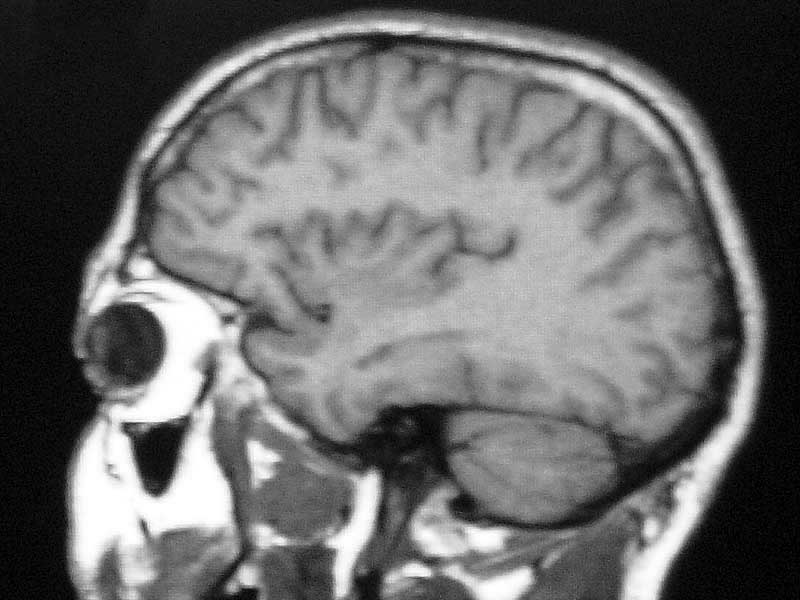

Up one "You need your head examining."

Beauty may be skin deep but

ugly goes right on through.